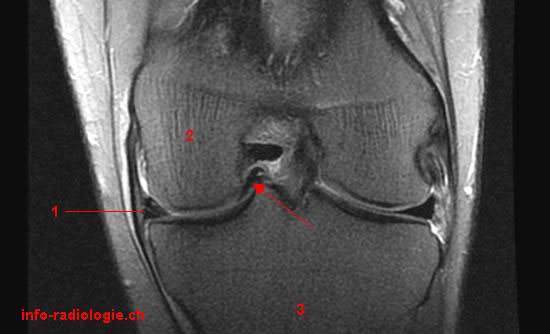

IRM du genou pour douleurs et hydarthrose récidivante: que voit-on?

Anse de seau du ménisque

Un patient a une sensation d’instabilité avec dérobement du genou, avec douleur et hydarthrose récidivante

Quel diagnostic?